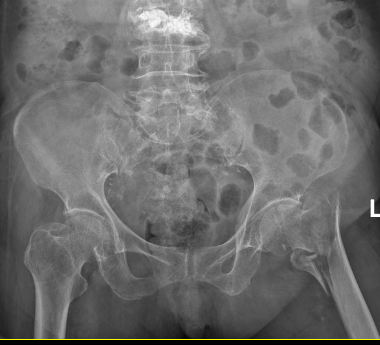

94岁高龄的莫婆婆,日前意外不慎摔倒,当即感到左髋部疼痛剧烈,无法站立行走。家人发现后,紧急将其送往我院就诊。经检查,老人被确诊为“左侧股骨粗隆间骨折”。

征得患者及家属同意后,手术当日,骨科一区医护团队密切配合,在C型臂X线机的精准引导下,仅通过几个微小切口,便顺利完成骨折闭合复位和内固定植入,手术过程顺利,出血量少,手术时间短。术后,莫婆婆生命体征平稳,被安全送回普通病房。

术前与术后